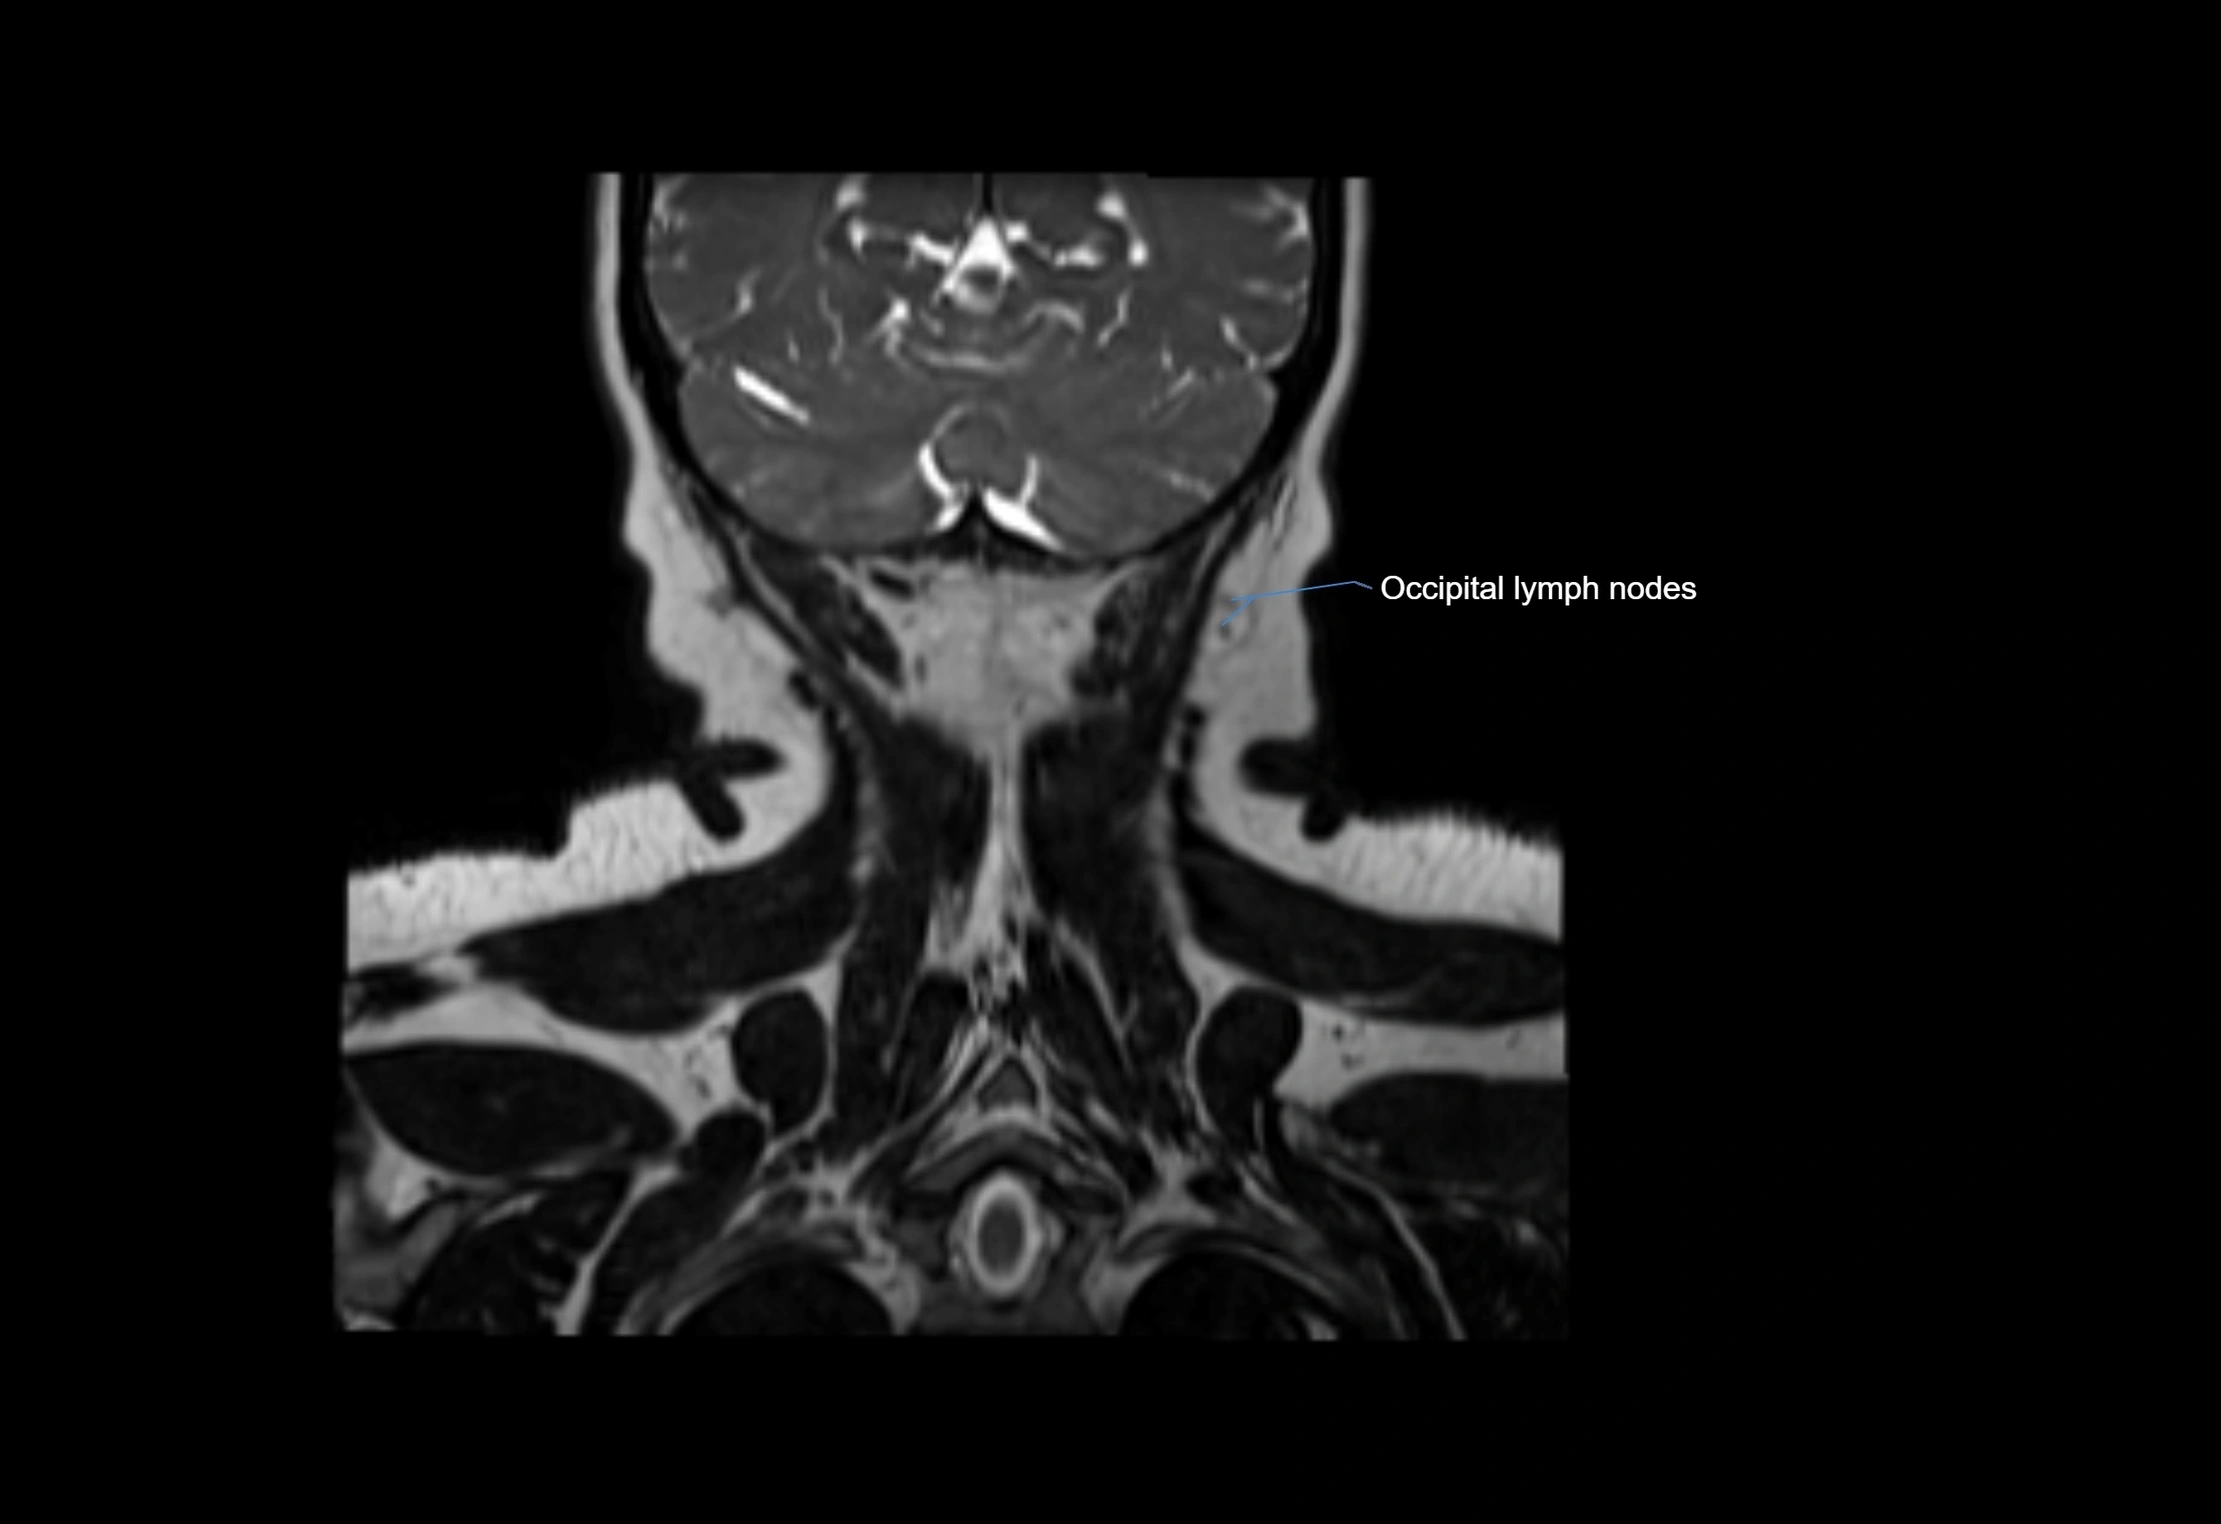

Accessory lymph nodes

Accessory lymph nodes are small, secondary lymph nodes located along the main facial and cervical lymphatic chains, often adjacent to primary lymph nodes, such as preauricular, submandibular, or occipital nodes. They are typically less than 5 mm in diameter, embedded within subcutaneous fat or connective tissue, and may be variable in number and location. These nodes provide additional filtration and immune surveillance for lymph collected from the face, scalp, and neck regions. Accessory lymph nodes are usually non-palpable in healthy individuals but may enlarge in response to infection, inflammation, or metastasis, making them clinically significant.

Location

• Found along primary lymph node chains, including preauricular, submandibular, parotid, and occipital regions

• Embedded in subcutaneous fat or superficial fascia, often lateral or posterior to primary nodes

• Variable in number; may occur unilaterally or bilaterally, depending on individual anatomy

T2-weighted images:

• Nodes show intermediate signal, with surrounding fat bright

• Useful for detecting edema, inflammation, or infiltration

• Fatty hilum may appear slightly hyperintense relative to cortex